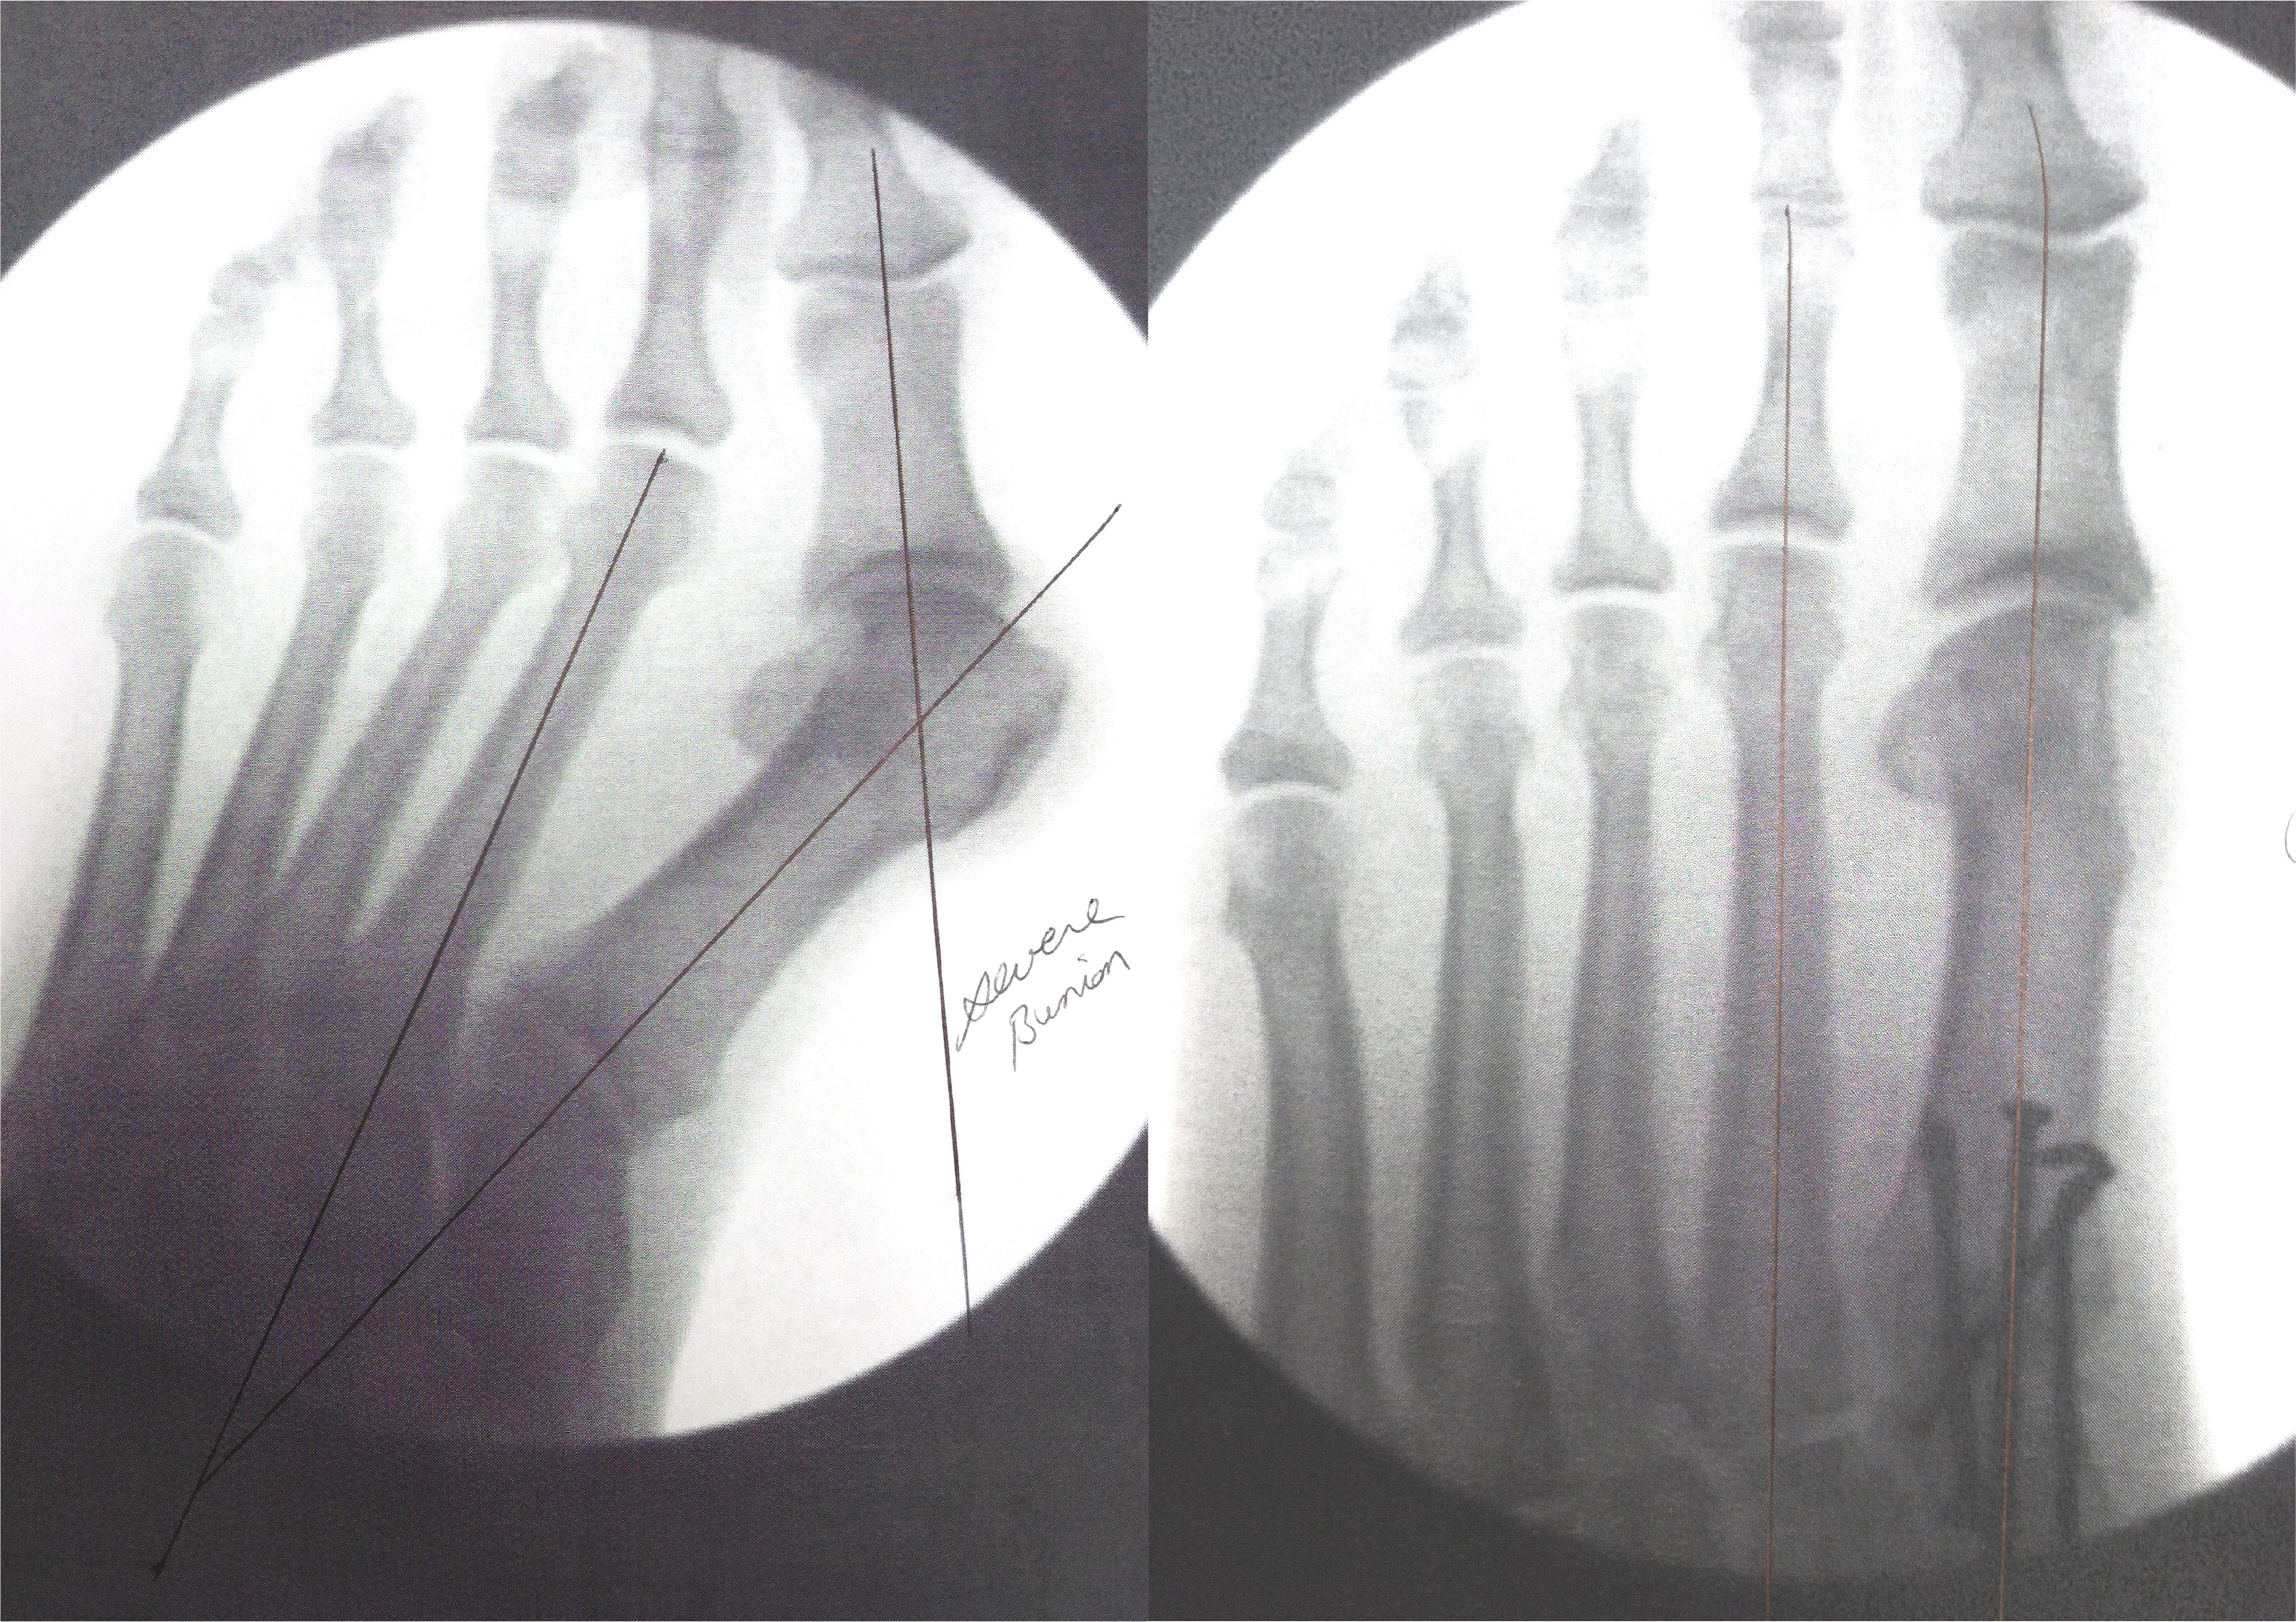

Bunions

Before

After